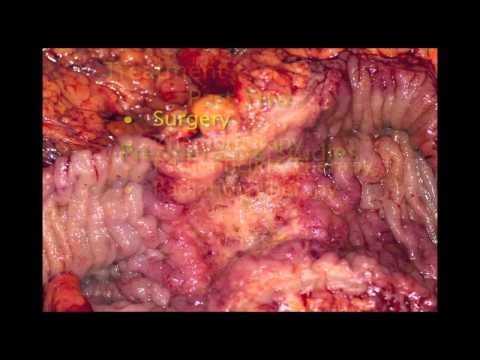

Kolektomia - wrzodziejące zapalenie jelita grubego

W materiale filmowym zaprezentowany jest zabieg kolektomii z powodu wrzodziejącego zapalenia jelita grubego. Zabieg wykonuje i szczegółowo komentuje Łukasz Dziki z Kliniki Chirurgii Ogólnej i Kolorektalnej...

20 do 25% pacjentów z rozległym wrzodziejącym zapaleniem jelita grubego ostatecznie przechodzi kolektomię, zwykle dlatego, że ich choroba nie zareagowała na leczenie farmakologiczne. W wrzodziejącym zapaleniu...

Ze względu na niekontrolowany i masywny krwotok pacjent przeszedł kolektomię. Widoczny fragment usuniętego jelita grubego.